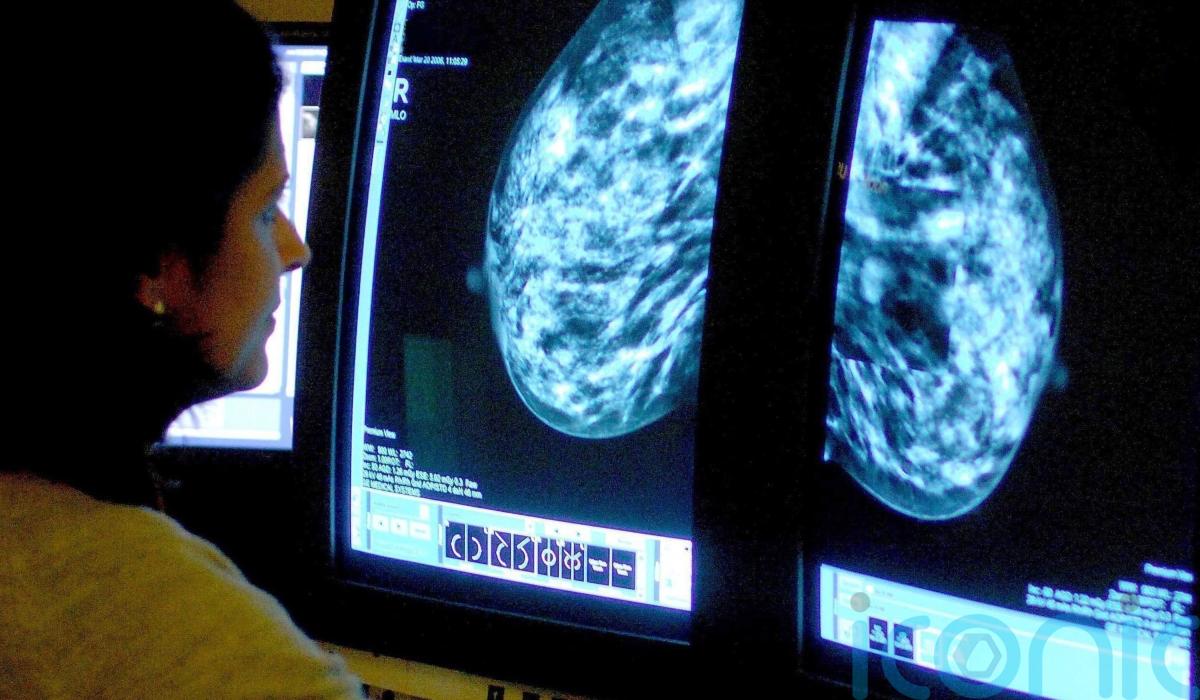

The importance of red flag referrals and screening routes for early diagnosis of cancer to improve survival rates for people in Northern Ireland has been highlighted in a report.

The study from the Northern Ireland Cancer Registry (NICR) at Queen’s University Belfast used research conducted on patients diagnosed between 2018 to 2020.

The Routes to Diagnosis report shows a strong relationship between a patient’s route to diagnosis and how advanced their cancer was at diagnosis.